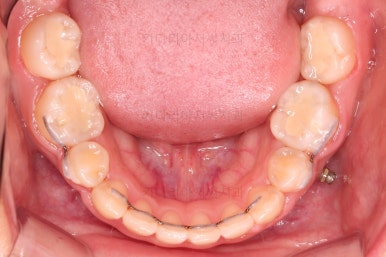

초진 때의 입안 모습입니다.

원래 다니던 치과에서 1년여 교정치료를 진행하신 상태였는데요.

몇 가지 이상한 점이 보이죠?

아랫니에 유치가 2개가 그대로 남아있다.(화살표)

우선 X-ray를 확인해 봤을 때, 아랫니 유치는 상태가 나쁘지 않아 그냥 쓰려면 한동안 계속 쓸 수는 있겠으나 영구치만큼 오래 쓸 수 있다는 보장이 없었고요.

해당 위치의 원래 영구치보다 크기가 커서 교합을 맞추는데 있어서도 문제가 있었어요.

딱 한 개의 치아만 발치되어 있었는데 추가적으로 균형을 맞추기 위해 반대편 치아도 발치를 하고 아랫니 유치도 뽑았어요.

유치 어금니는 크기가 매우 크기 때문에 빈자리 만큼 모두 앞니를 뒤로 당기면 입이 너무 들어가게 된답니다.

따라서 얼마나 효과적인 방법으로 적절한 양만큼 어금니를 앞으로 당겨올 것인가가 이번 치료의 핵심이었어요.

아랫니는 아무 생각 없이 당기기 해주면 앞니가 너무 들어가 입이 합죽해질 수 있으니 앞니가 들어가는 양을 조절하기 위해서 미니스크류를 사용해주어요.

적절한 시기부터는 어금니만 100% 앞으로 당겨와야 했기 때문이죠.